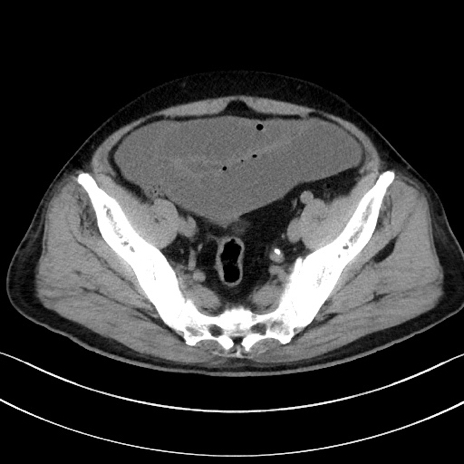

症例15(横断像)

【症例】70歳代男性

【主訴】腹痛

【現病歴】今朝から腹痛あり。全体的に痛い。特に左上の方。排ガスが今日はない。冷や汗が出る。

【既往歴】直腸癌術後

【身体所見】左側腹部〜上腹部に圧痛あり。腹膜刺激症状明らかなではない。軽度反跳痛。左下腹部に術後瘢痕あり。

【データ】WBC 7700、CRP 0.02